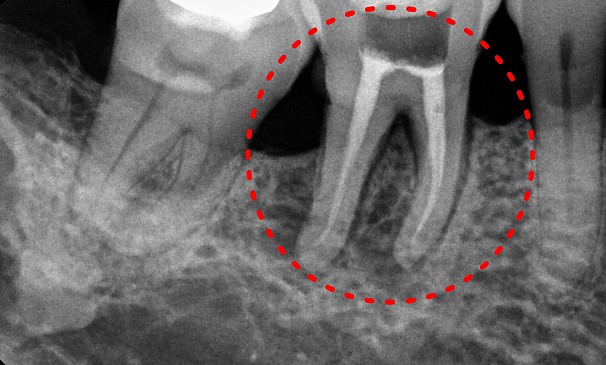

방OO님 전후사진 | 치료 기간 : 3주

치료 전

치료 후

특수신경치료